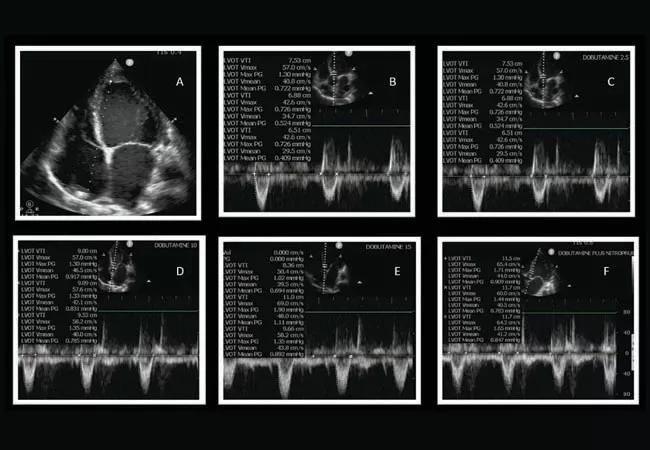

Figure A: The image shows a dilated left ventricle. Figures B – E: The images show increase in LVOT VTI (surrogate for stroke volume/cardiac output) with increase in dobutamine dosage from the 15 µg/kg/min shown in Figure E. Figure F: The image shows additional increase in LVOT VTI (surrogate for stroke volume/cardiac with addition of nitroprusside.

breathing trial attempts were associated with tachycardia, tachypnea and increased lactate levels. A chest X-ray was performed to determine the etiology of the patient’s spontaneous breathing trial (SBT) failure and showed minimal bibasilar infiltrates. A bedside (POCUS) cardiac assessment was performed, which showed severely dilated and severely reduced left ventricular cardiac function. The POCUS was also used as a hemodynamic monitoring device to measure stroke volume and cardiac output with validated pulse wave Doppler LVOT VTI technique. The cardiac output was found to be significantly reduced in comparison to the previous echocardiogram.

The patient’s failure to transition from the mechanical ventilator to spontaneous breathing was attributable to his compromised left ventricular systolic function. The patient was started on dobutamine, an inotropic agent to increase cardiac output. The medication was titrated using POCUS-guided cardiac output measurement.

Once it was observed that up-titration of dobutamine further increased cardiac output, nitroprusside was added. The optimal dosage of nitroprusside was again guided by trending the cardiac output, obtained using POCUS. Over the next 24 hours, the cardiac output was optimized using POCUS, and the patient was successfully extubated. Following the transition from intravenous medication to oral medication, the patient was discharged home.